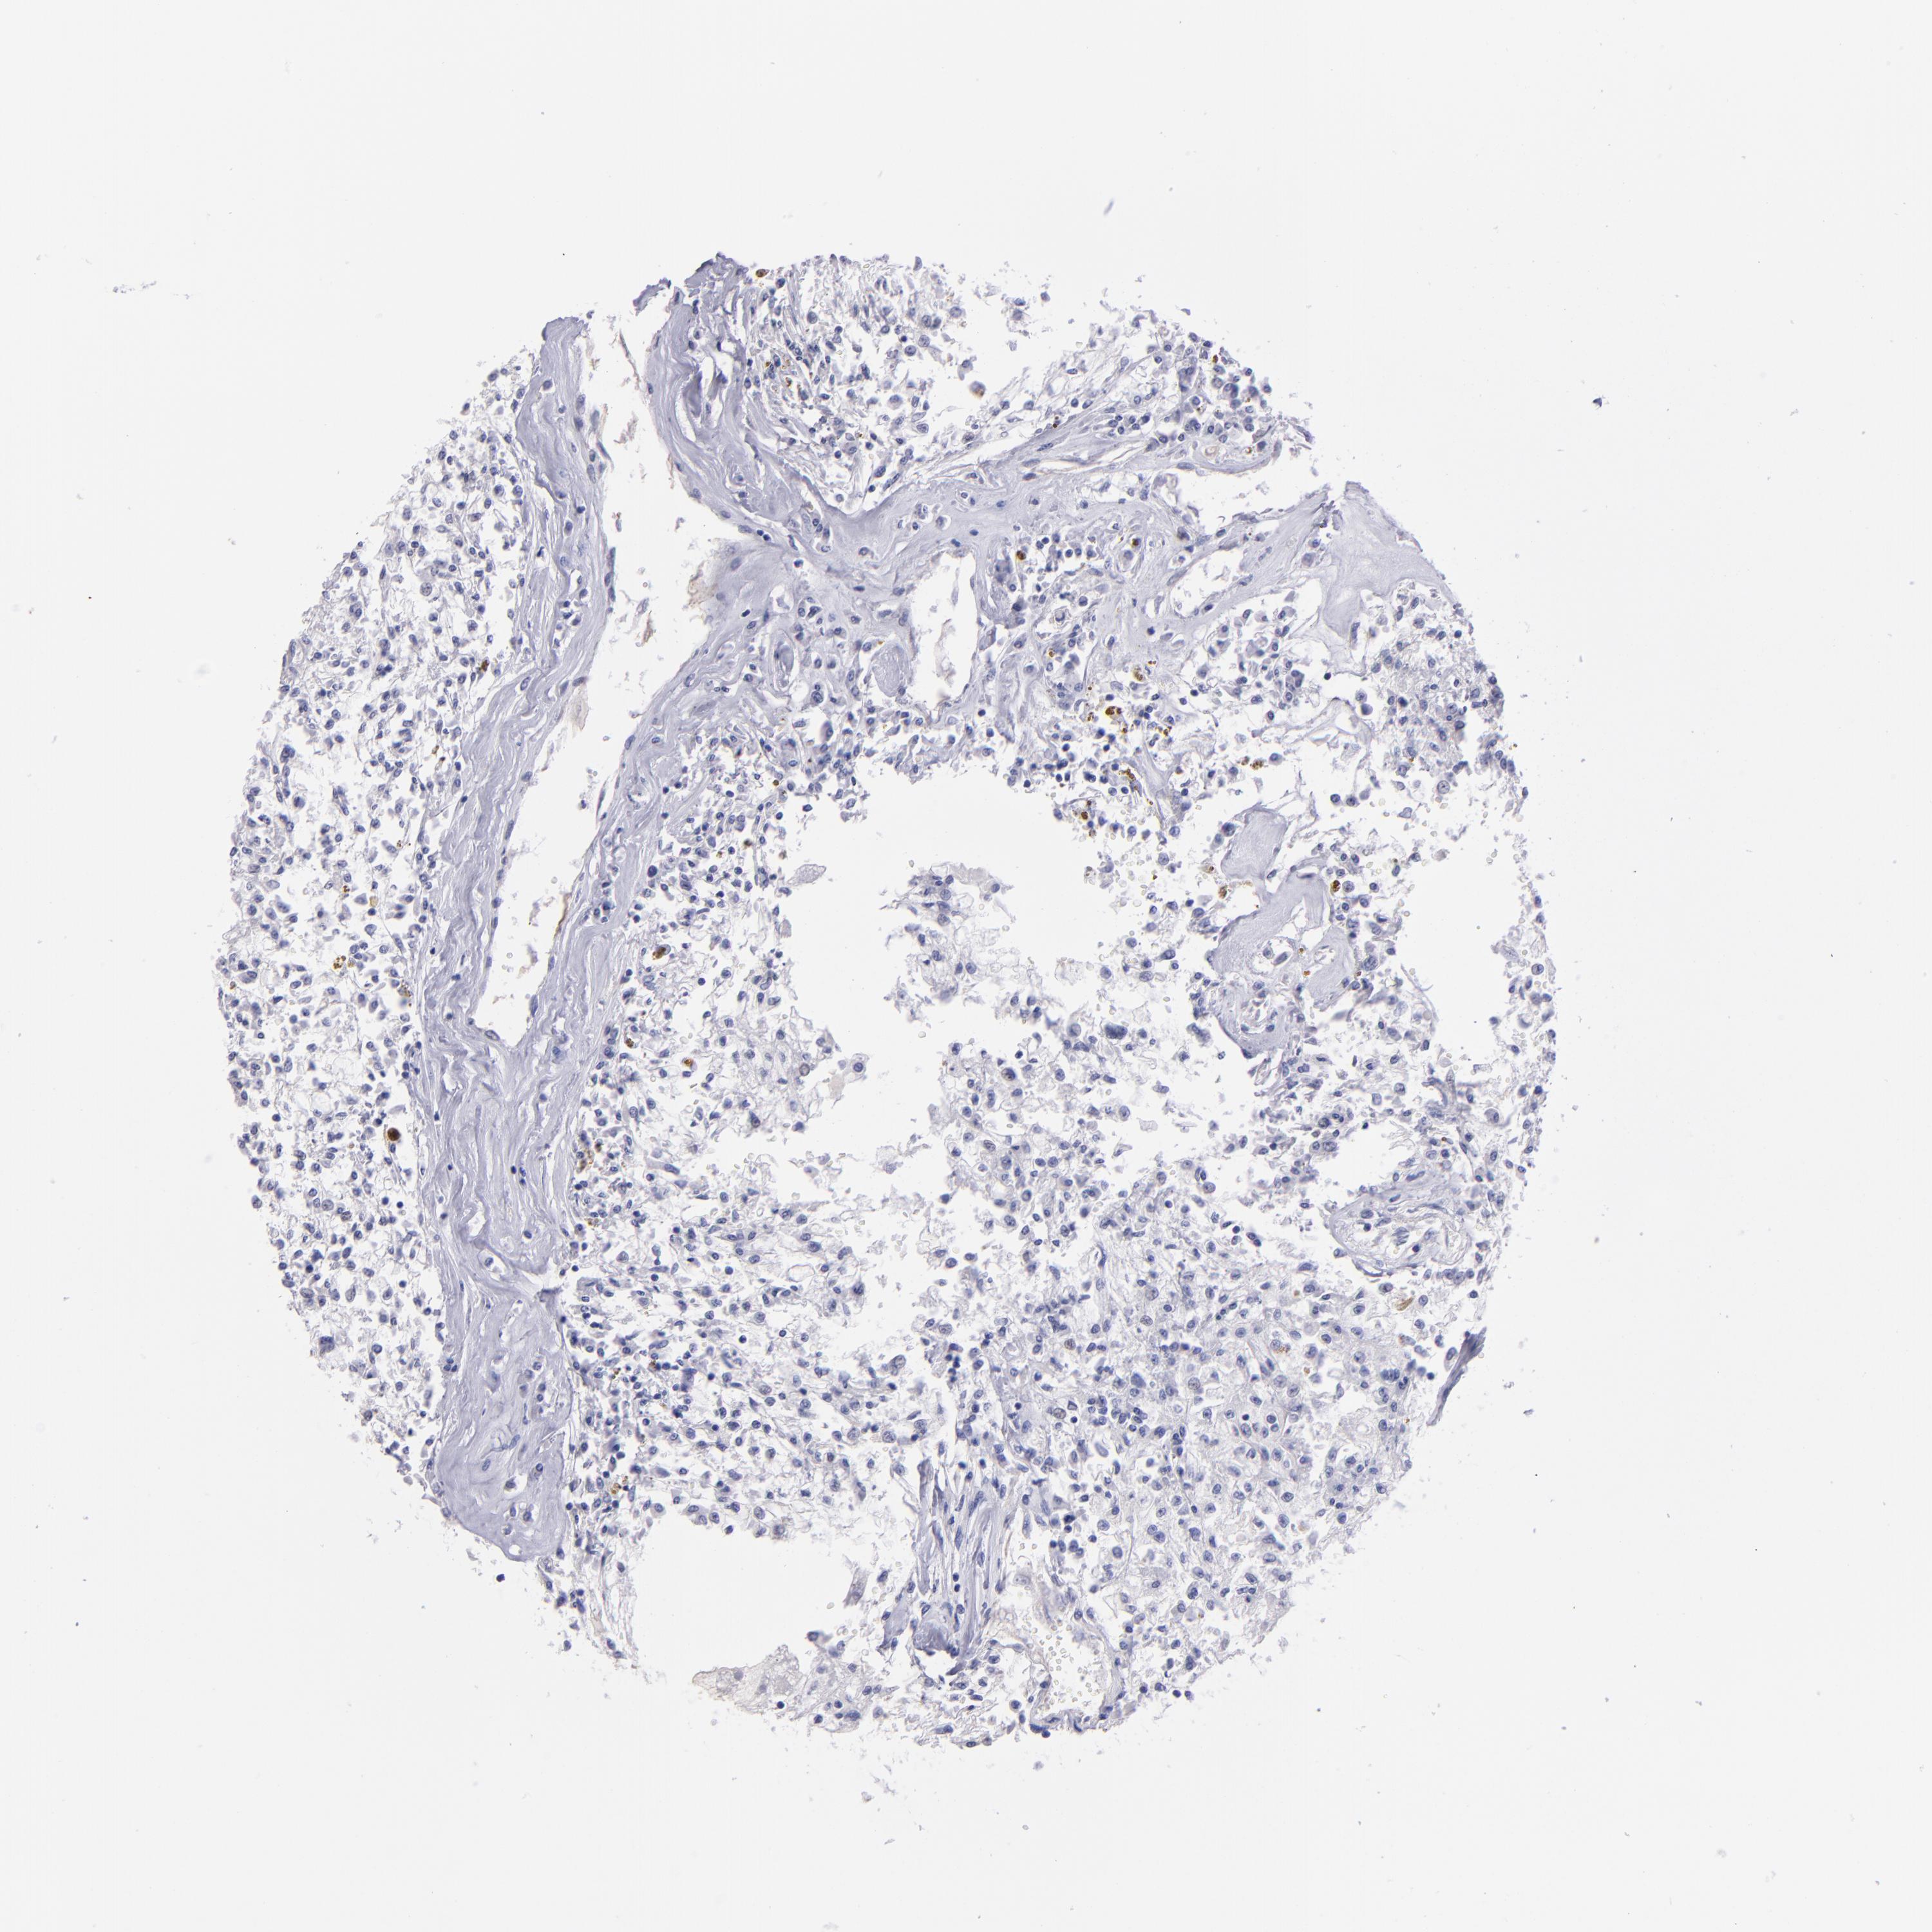

KIDNEY RENAL PAPILLARY CELL CARCINOMA (TCGA) - Interactive survival scatter ploti

The Survival Scatter plot shows the clinical status (i.e. dead or alive) for all individuals in the patient cohort, based on the same data that underlies the corresponding Kaplan-Meier plots. Patients that are alive at last time for follow-up are shown in blue and patients who have died during the study are shown in red.

The x-axis shows the expression levels (FPKM) of the investigated gene in the tumor tissue at the time of diagnosis. The y-axis shows the follow-up time after diagnosis (years). Both axes are complimented with kernel density curves demonstrating the data density over the axes. The top density plot shows the expression levels (FPKM) distribution among dead (red) and alive patients (blue). The right density plot shows the data density of the survived years of dead patients with high and low expression levels respectively, stratified using the cutoff indicated by the vertical dashed line through the Survival Scatter plot. This cutoff is automatically defined based on the FPKM cutoff that minimizes the p-score. The cutoff can be changed by dragging the vertical line or by entering a cutoff value in the square labeled "Current cut-off".

Under the Survival Scatter plot the p-score landscape (black curve; left axis) is shown together with dead median separation (red curve; right axis). Dead median separation is the difference in median mRNA expression between patients who have died with high and low expression, respectively. It is calculated as follows: median FPKM expression of dead patients with high expression - median FPKM expression of dead patients with low expression. This is intended to aid the user in visually exploring custom cutoffs and the associated p-scores and dead median separation.

Individual patient data is displayed and can be filtered by clicking on one or more of the category buttons on the top of the page. Categories describing expression level and patient information include: high, low, alive, dead, female, male and tumor stages. The scale of the x-axis can be toggled between linear and log-scale by clicking on the "x log" button. Mouse-over function shows TCGA ID, patient information and mRNA expression (FPKM) for each patient.

& Survival analysisi

Kaplan-Meier plots summarize results from analysis of correlation between mRNA expression level and patient survival. Patients were divided based on level of expression into one of the two groups "low" (under cut off) or "high" (over cut off). X-axis shows time for survival (years) and y-axis shows the probability of survival, where 1.0 corresponds to 100 percent.

TG is not prognostic in Kidney Renal Papillary Cell Carcinoma (TCGA)

Best expression cut offi

Based on the FPKM value of each gene, patients were classified into two groups and association between prognosis (survival) and gene expression (FPKM) was examined. The best expression cut-off refers the FPKM value that yields maximal difference with regard to survival between the two groups at the lowest log-rank P-value. Best expression cut-off was selected based on survival analysis .

When clicking on this number, the vertical dashed line indicating cut-off, the interactive survival plot, and the Kaplan-Meier curve will be adjusted to show results based on the best expression cut-off.

: 1.19